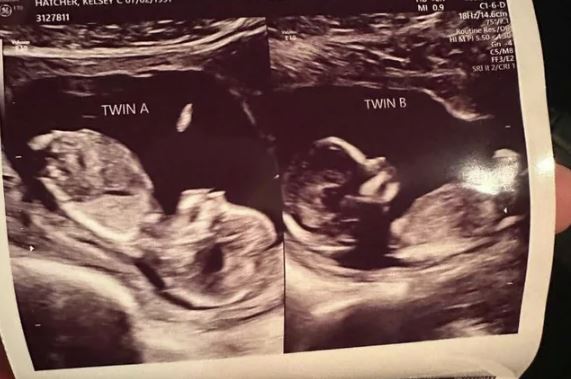

Μια γυναίκα από την Αλαμπάμα με δύο μήτρες κυοφορεί από ένα κοριτσάκι σε κάθε μία σε μια «απίστευτη» εγκυμοσύνη, όπως λένε οι γιατροί.

Η 32χρονη Κέλσι Χάτσερ, μητέρα ήδη τριών παιδιών, γεννήθηκε με μια σπάνια ανωμαλία, που ονομάζεται δίδελφυς μήτρα, δηλαδή με δύο μήτρες.

Η γυναίκα το έμαθε την περασμένη άνοιξη, όταν διαγνώστηκε ότι είναι έγκυος και στις δύο μήτρες. Όταν είπε τα νέα στον άνδρα της, εκείνος αδυνατούσε να την πιστέψει.

Όπως αναφέρει η βρετανική εφημερίδα The Guardian, μόλις ένα ποσοστό γύρω στο 0,3% των γυναικών εμφανίζουν τη συγκεκριμένη ανωμαλία, που σχηματίζεται σε πρώιμο στάδιο της κύησης, περίπου στις οκτώ εβδομάδες, στο θηλυκό έμβρυο. Στην περίπτωση της Χάτσερ «είναι εκπληκτικό το γεγονός ότι και οι δύο μήτρες είχαν ωορρηξία την ίδια, ή περίπου την ίδια χρονική στιγμή», δήλωσε η δρ Χέιλι Μίλερ, μέλος της Αμερικανικής Ένωσης Γυναικολόγων και Μαιευτήρων.

Τα μωρά μπορεί να γεννηθούν με διαφορά ωρών ή ημερών καθώς οι δύο μήτρες μπορούν να κάνουν τις συσπάσεις ανεξάρτητα. Οι γιατροί της 32χρονης υπογράμμισαν τους κινδύνους καισαρικής τομής σε μια γυναίκα με δύο μήτρες, όπως ότι η απώλεια αίματος μπορεί να είναι μεγαλύτερο αφού θα χρειαστούν δύο τομές. Η Χάτσερ αναμένεται να φέρει στον κόσμο τα κοριτσάκια της ανήμερα των Χριστουγέννων, σύμφωνα με το τοπικό δίκτυο WVTM, ενώ δεν έχει ακόμη αποσαφηνιστεί αν τα μωρά θα μπορούν να θεωρούνται δίδυμα, αφού δεν αναπτύχθηκαν στην ίδια μήτρα.